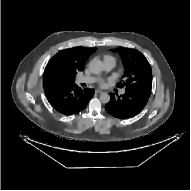

This section compares the reconstruction quality and runtime among the proposed MBIR method, PWLS-ST-, and other three MBIR methods, PWLS-EP, PWLS-DL, and PWLS-ST-. Table I shows that, for both 2D and 3D sparse-view CT reconstructions of the XCAT phantom, the proposed PWLS-ST- model outperforms PWLS-EP and PWLS-ST- in terms of RMSE. In addition, PWLS-ST- using a square transform (of size ) achieves lower RMSE than PWLS-DL using an overcomplete dictionary (of size ) for 2D sparse-view reconstructions. Fig. 3(a) and Fig. 4 show the reconstructed images for 2D and 3D phantom experiments, with different reconstruction models and different number of views. (See the corresponding error maps in the supplement.) The proposed PWLS-ST- consistently gives more accurate image reconstructions compared to other MBIR methods. Specifically, PWLS-ST- has smaller errors in the heart region (see zoom-ins in Fig. 3(a)) of 2D reconstructions than PWLS-DL and PWLS-ST-. In addition, compared to PWLS-ST-, PWLS-DL and PWLS-ST- have some ringing artifacts around the edges with high transition, e.g., edges between air and soft tissues. (See a comparison of profiles of PWLS-ST- and PWLS-ST- in the supplement.) In particular, PWLS-ST- and PWLS-DL give more visible ringing artifacts for 2D reconstruction from fewer views, and PWLS-ST- has these ringing artifacts for 3D reconstructions regardless of the number of views (see zoom-ins in Fig. 4). Table II reports runtimes of different MBIR methods in reconstructing the -views XCAT phantom scan. (FBPConvNet is a non-MBIR method and its runtime for processing a image is approximately one second with a TITAN Xp GPU.) While providing better reconstruction quality, the proposed Algorithm 1 of PWLS-ST- has shorter runtime compared to the algorithms of PWLS-DL and PWLS-ST- in Section III-A. Similar to the PWLS-EP algorithm, the reconstruction time of the PWLS-DL, PWLS-ST-, and PWLS-ST- algorithms can be further reduced by using ordered subsets [51].

![]() |

| (b) 3D axial cone-beam CT experiments |